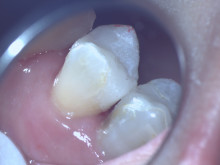

なかなか肉眼ではきれいになってるのを確認できません。

マイクロスコープでみると一目瞭然です。 |

マイクロで確認しながら、洗浄を繰り返すときれいになっているのがわかります。 |